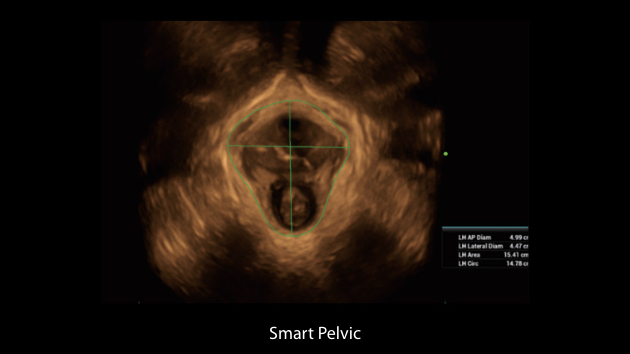

The Nuewa I9 Elite Edition, dedicatedly designed for women and neonatal healthcare, providing an innovative experience from inside out. These innovations are developed based on in-depth insights into complex clinical scenarios, providing accurate and timely answers as well as outstanding efficiency and remarkable user experience